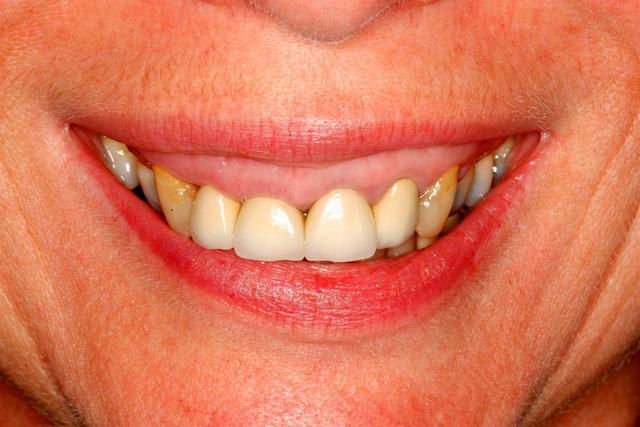

Suite du p'tit cas de ré-hab.

Cirage (wax-up en français ;-))

Gain en vertical et en AP (antéro-postérieur)

Disparition de la Cl-2 par callage postérieur et repositionnement mandibulaire.

Prochaine étape, placer cela en bouche (provisoires).

A suivre...(le cas est en cours, faut être patient)